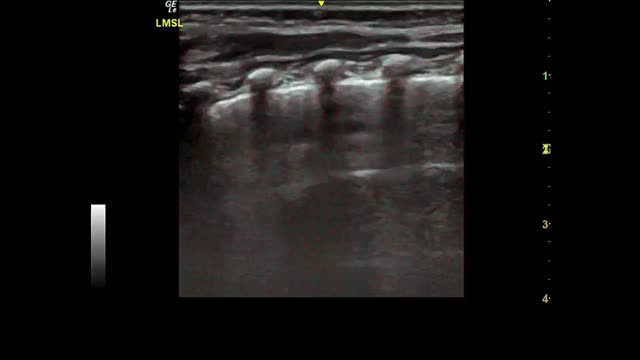

Fig. 2 shows the main findings of the LU imaging described in the study.